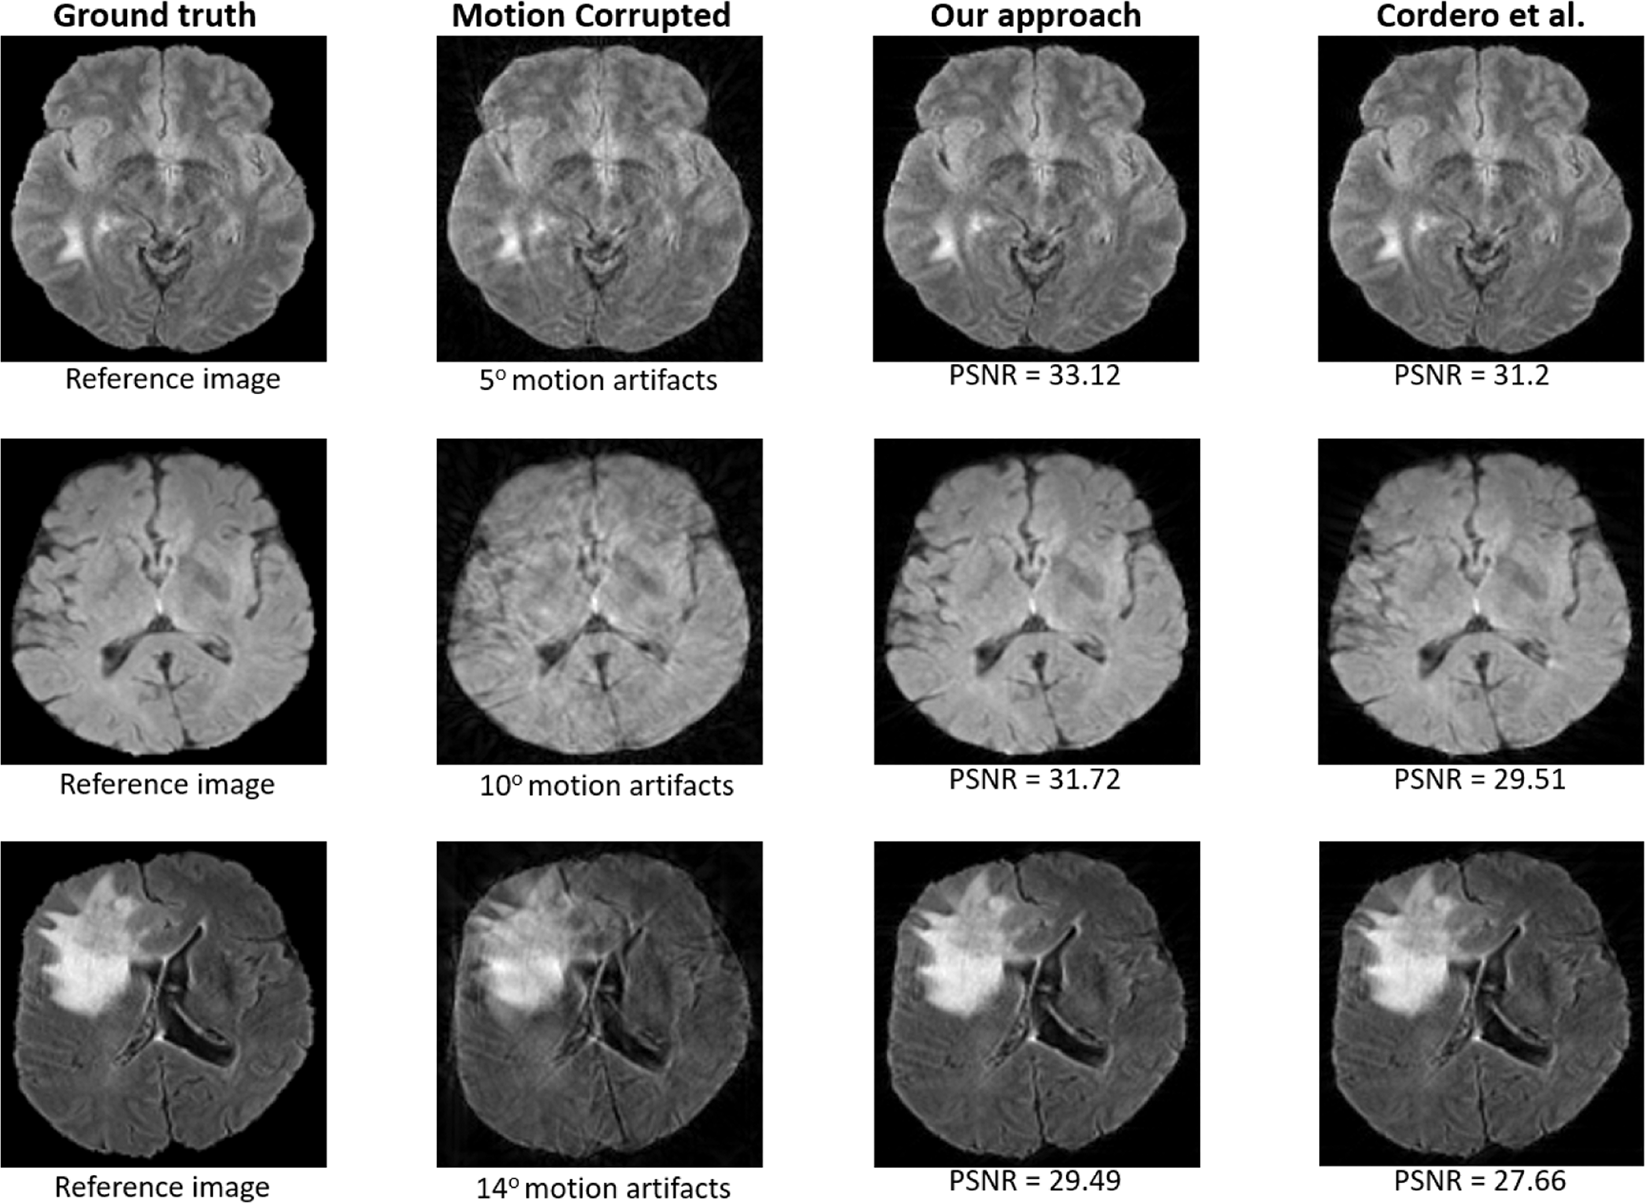

Figure 4

From: Retrospective Motion Correction in Multishot MRI using Generative Adversarial Network

Resultant images produced by our approach compared to those produced by Cordero et al.25 for Δθ = {5°, 10°, 14°} with 16-shot and random trajectory.